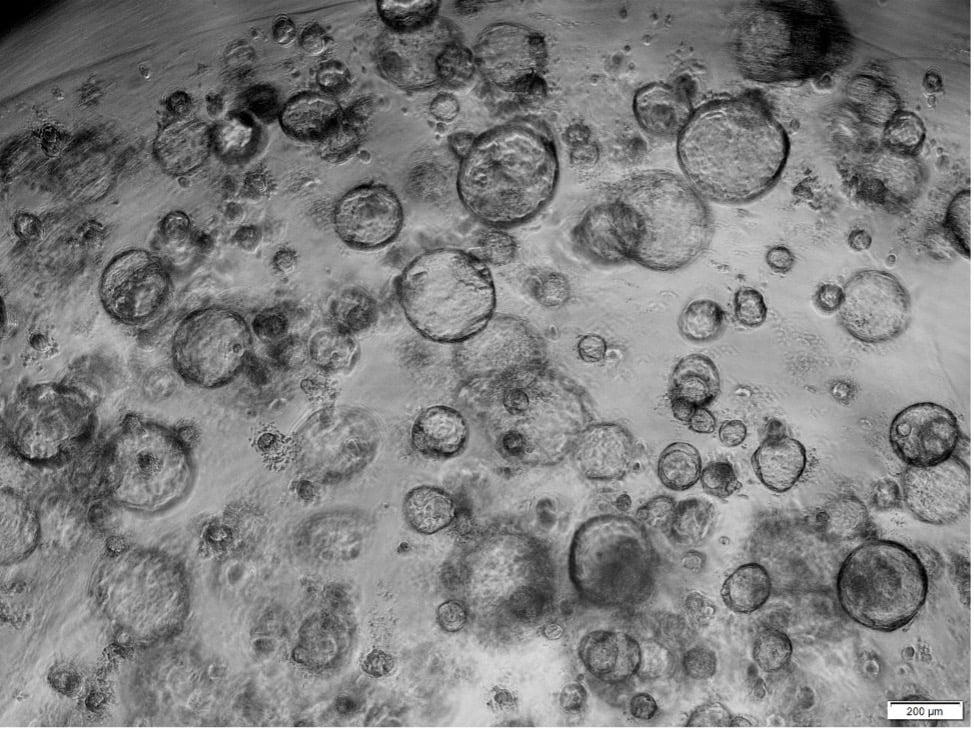

If you already have experience in expanding primary cells, the step to 3D cell culture is not a big one. Every 3D culture begins with an expansion of the cells in 2D. For airway organoids, primary human bronchial epithelial cells can be used for this purpose. It should be noted that primary cells have a finite lifespan. With increasing population doubling, the ability of cells to differentiate can decrease. This must be considered if you want to differentiate the cells later. For the 3D cultivation of bronchial epithelial cells, we have developed a robust air-liquid interface medium that is qualified for a long-lasting, measurable barrier function over a period of at least 4 weeks. We found that this medium was not only suitable for a functional culture on porous membranes, but also for a functional 3D culture in an ECM. Both applications were developed according to best practice guidelines. We were able to gain a lot of experience during the establishment of both protocols. When working with biological systems, the susceptibility to failure is very high. It is therefore important to use as many robust constants as possible. Not every tissue donation is suitable for generating bronchial epithelial cells capable of differentiation. In order to qualify cell batches for the 3D cell culture, cell batches need to be screened in a time-consuming manner. Other possible confounding factors include cell culture plastic and ECM. In the case of cell culture plastic, it must be said that with organoid technology it is essential that the plastic has non-adhesive properties, otherwise the cells may adhere to the plastic surface and not remain in suspension. If you want to perform high-throughput experiments on your 3D organoid cultures, 96-well plates with U-bottom are recommended. Even with small wells, the cells can be well distributed in the ECM and are easy to examine under the microscope. Various ECM variants for organoids can be found in the literature, with commercial basement membrane matrix occurring frequently. With ECM we have had good experiences using commercial basal membrane extract obtained from Engelbreth-Holm-Swarm (EHS) mouse sarcoma cells. In addition to the numerous adhesive proteins, this matrix also contains growth factors such as TGF-ß or EGF. These growth factors are known regulators of proliferation and differentiation. A growth-factor-reduced basal membrane extract should therefore be used to prevent possible suppression of differentiation. It should also be noted that there are different orientations for the airway organoids. With airway organoids, a distinction is made between apical-in and apical-out models. This describes the orientation of the polarized epithelial cell layer, which can be very well distinguished from one another microscopically. The ciliated cells point outwards in the apical-out model. This has the advantage that these cells are freely accessible for experiments. For example, in order to stimulate the polarized epithelial cells, one does not need to microinject for example, virus material or mechanical fragmentation of the apical-in models. It is already known that the orientation of cell polarity can be influenced by the ECM.

Differentiation of HBEpC after 16 days of 3D culture in ALI-Airway. Bright-field microscopy shows the polarized epithelial cell lining of the organoids and the inner central lumen. Arrows indicate differentiated, outside oriented ciliated cells. Scale bar = 20 µm.

Airway organoids with self-renewal potential can be used for longterm culture.

From a technical point of view apical-in airway organoids can be detached from the ECM and then triggered to apical-out in an ECM-free suspension culture. However, a disadvantage of this structural organoid switch is that many organoids lose their integrity and, for example, fuse with other organoids. With our Application Note, we have succeeded in creating a simple protocol for the 3D cultivation of bronchial epithelial cells that favors the generation of apical-out models.